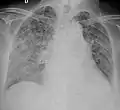

A case of miliary tuberculosis in an 82-year-old woman:

X-ray, 22 days after onset, showing extensive bilateral reticulo-nodular infiltrates